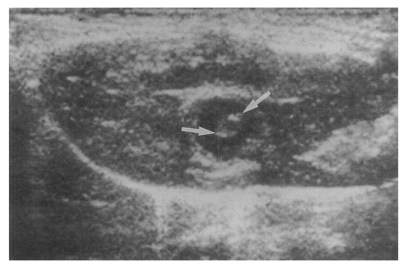

Sonography showed no dilatation of the bile duct confluence in the normal control group (Fig. 3). Sonograms showed moderate or marked dilatation of the bile duct confluence in the primary infection control group, the secondary infection control group, and the reinfection II group (Fig. 4, Table 2). A small number (1 of 7 in all groups) of animals showed mild dilatation of bile duct confluence in these groups (Fig. 5, Table 2). Dilated extrahepatic bile ducts were also observed. In the reinfection I group and the infection following immunization group, the degree of dilatation of the bile duct confluence was usually moderate (in n = 4 and n = 5, respectively). Marked dilatation was less frequent in these groups (n = 2 in each group).

High echogenicity closely packed at the dilated bile duct confluence was seen in all rats in the primary or secondary infection control groups; however, this was seldom noted in the reinfection I (n = 1) and reinfection II groups (n = 0) (p = 0.005 and p = 0.001, respectively) (Fig. 6). The echogenic mass was found to be composed of clusters of worms and desquamated materials by pathological examination. Small echogenic foci were noted in the dilated bile duct confluence in the infection following immunization group. These also represented worms and desquamated materials (Fig. 7). In the reinfection I and II groups, the degree of dilatation of the bile duct confluence on the last follow-up sonograms at 26 weeks after reinfection were noted to be slightly milder than those at 6 weeks after reinfection, but this was not significant (p = 0.266 and p = 0.431, respectively) (Table 2).

Fig. 4

Sonogram of a rat in the primary infection control group 4 weeks after C. sinensis infection, showing marked dilatation of the bile duct confluence (arrows) with high echogenicity, reflecting worm burden and desquamated materials.

kjp-42-7-g004.jpg